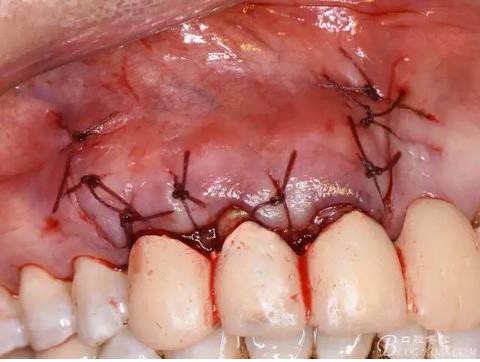

圖18.骨腔填塞膠原蛋白海綿

圖19.縫合